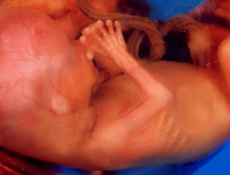

- Fóstrið vegur nú um 18 gr og lengd þess er um 6 cm.

- Nú lýkur fyrsta þriðjungi meðgöngunnar. Fósturlátshættan er að mestu liðin hjá og flestum konum fer að líða vel. Ef við líkjum meðgöngunni við flugferð, þá getum við sagt að nú sé flugtaki lokið og flestar konur sigla/fljúga nokkuð lygnan sjó næstu vikurnar.